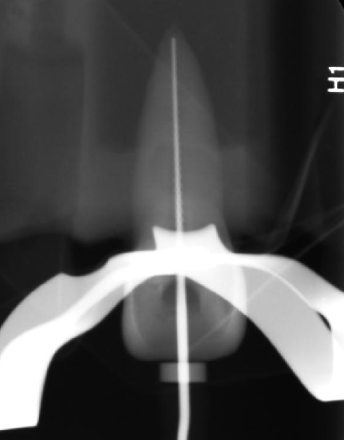

Working length is the distance from

A coronal reference point tot he point at which canal preparation and obturation should terminate

When should the the apex terminate?

0.5-1mm from radiographic apex

For the working length, if there is difficulty viewing the file, you can use

A 15K file or larger

How can you create a repeatable reference?

Make sure the reference point is touching the stopper (incisal edge or cusp)